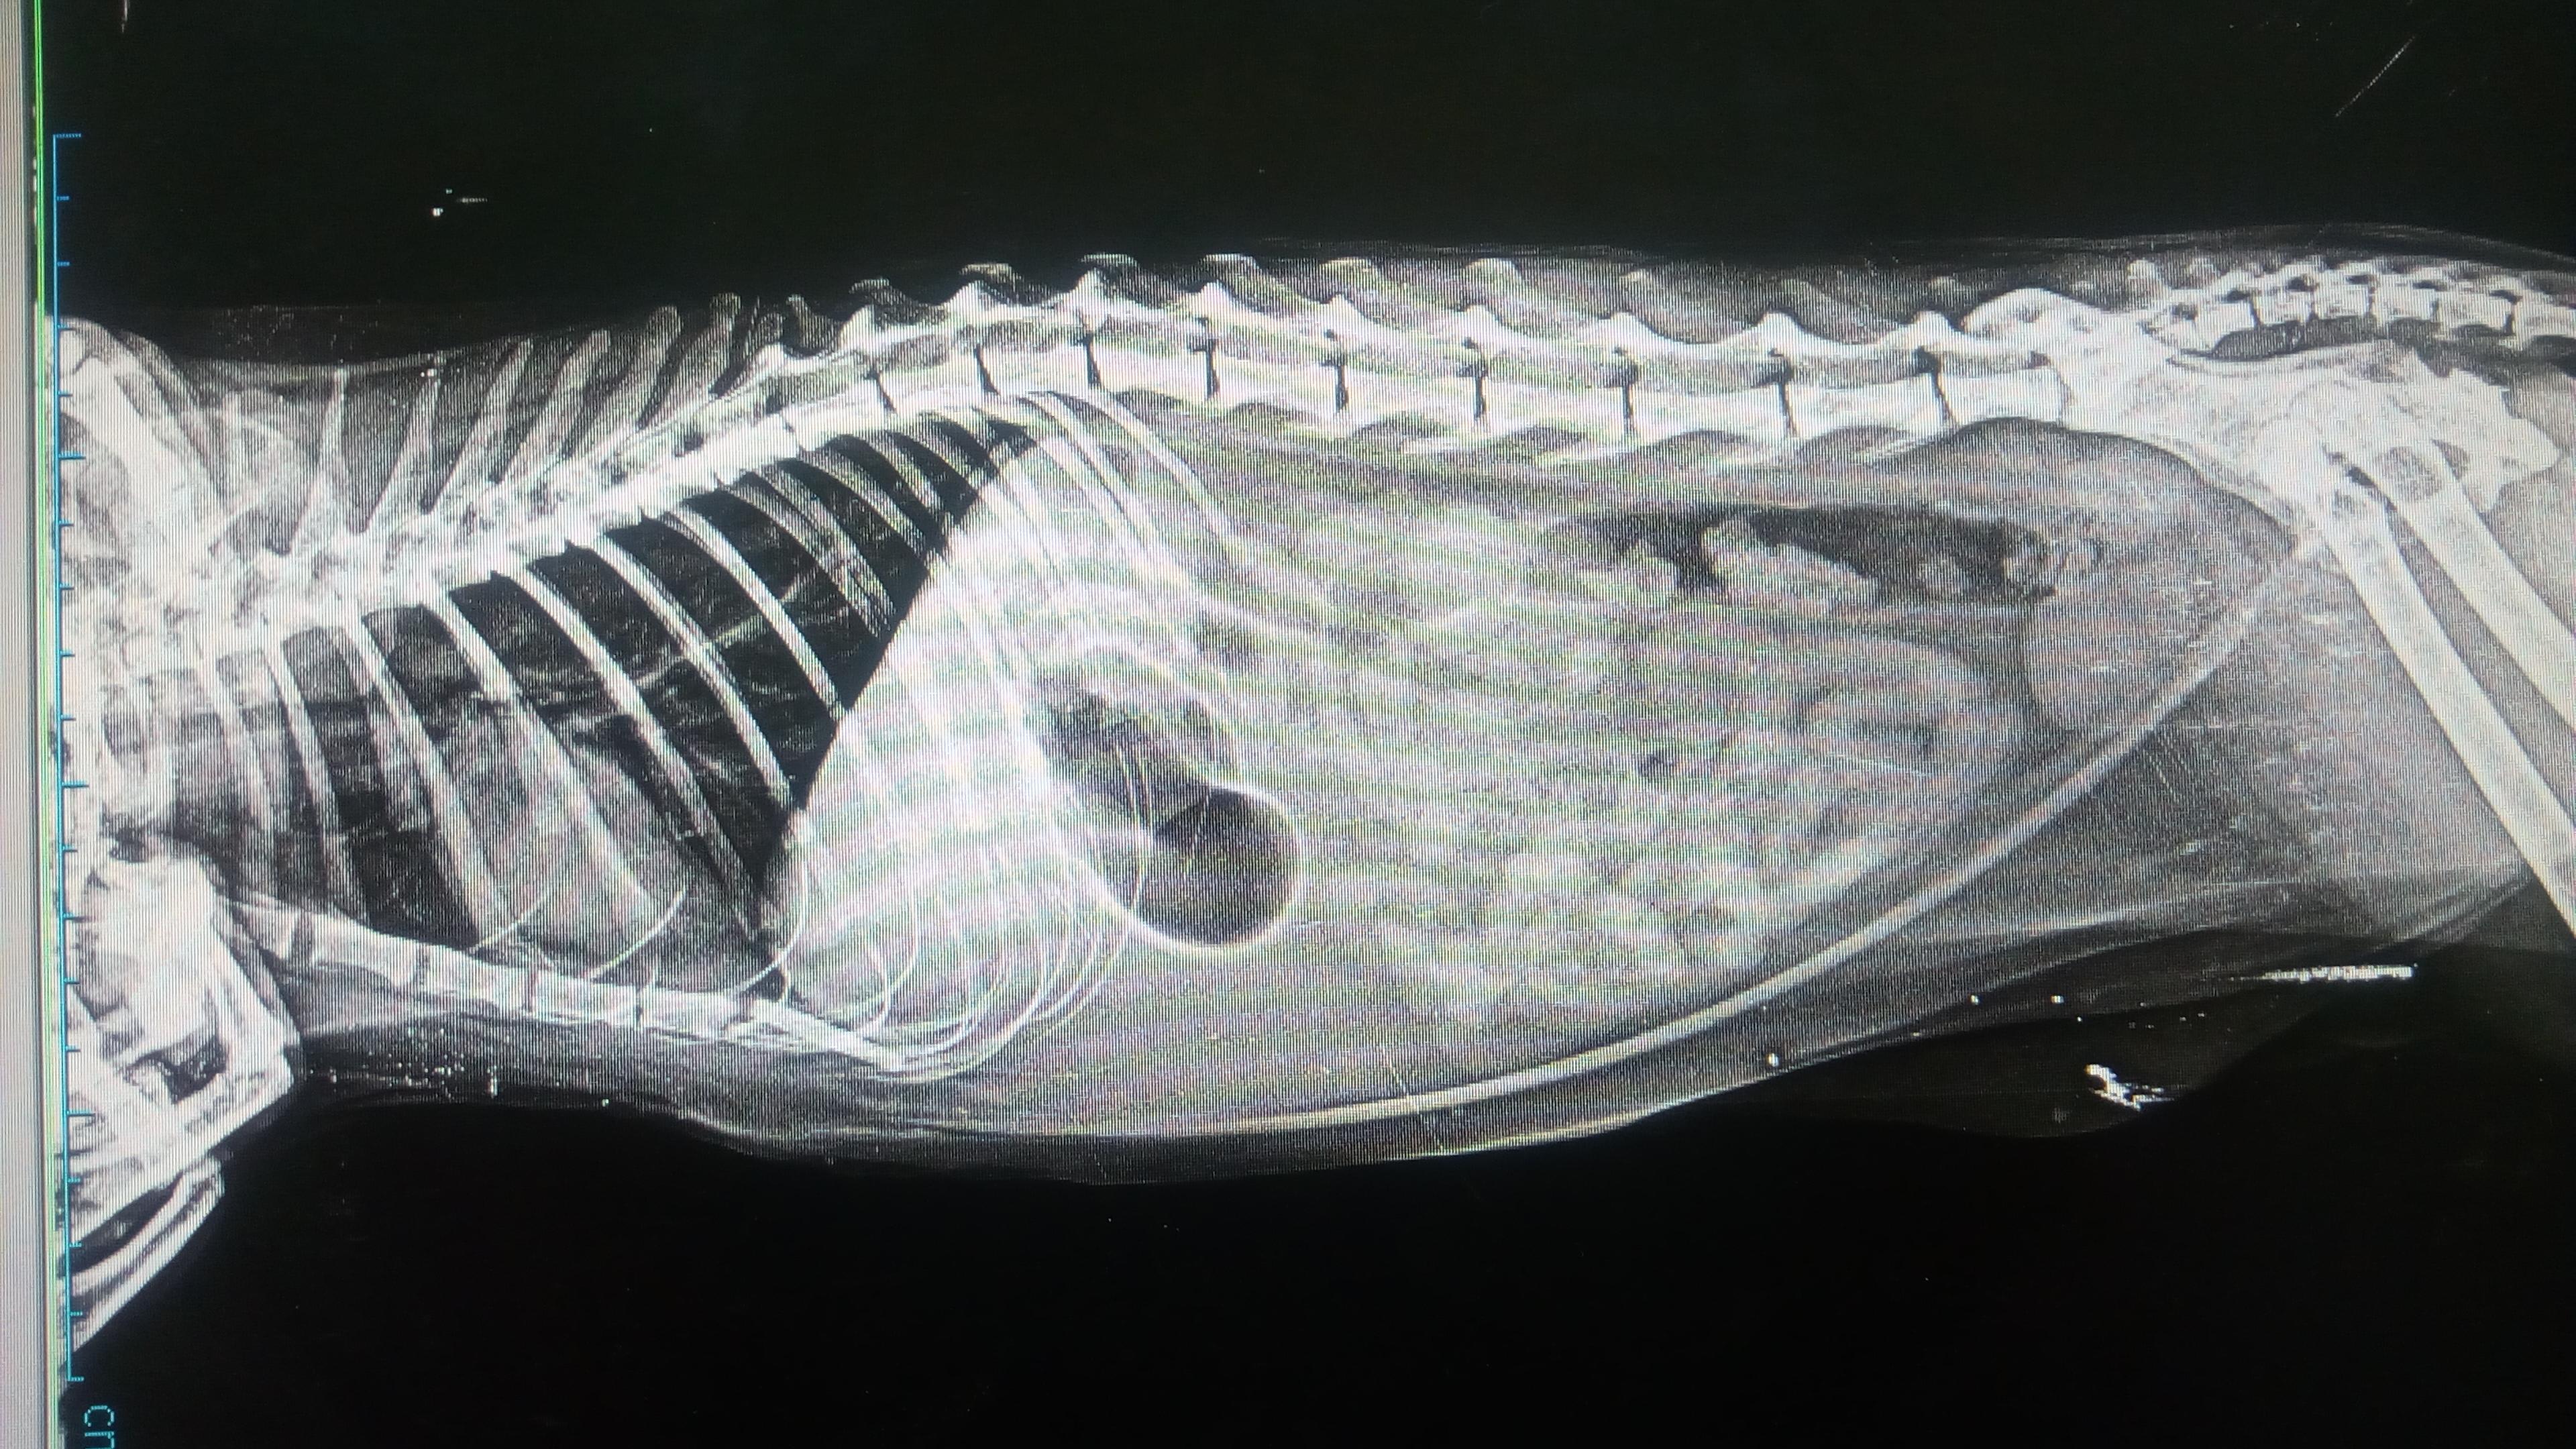

a week ago my cat stopped eating & started to throw up then he was drinking lots of water & throwing up an he did that constantly then he got hypothermia & started to shake and get dizzy & couldn't move so we took him to the vet he give him IV fluids to raise his temperature then he took x-ray of him & said that he have a severe gastritis and his Liver size is bigger a bit so he give him IV fluids & antibiotic for 3 days after that he did stop throw up but after 1 day he throw up again plz help

I am sorry for the delay in answering your question... I hope that Iomy is feeling better! Based on his xray, it does appear that his liver may be a bit enlarged. If he is still showing symptoms of illness, ask your family veterinarian about an abdominal ultrasound. This may help clarify what the problem is and what your options are. Also, if blood tests haven't been done that would also be helpful. Again, I hope you he is feeling better.... if you have additional questions please feel free to post on the forum and we will do our best to help!